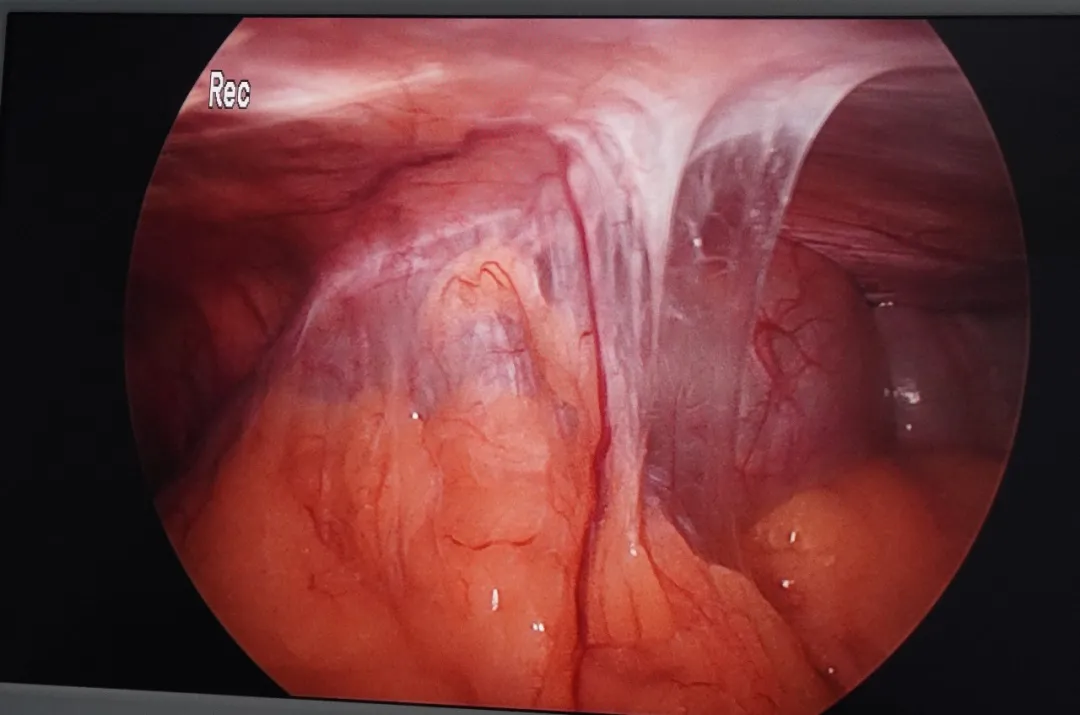

当腹腔镜探查镜头探入腹腔的那一刻,情况果然如术前所料:腹腔内广泛粘连,腹腔内形成了致密的“蜘蛛网”,所幸胆囊没有包裹其中,解剖层次相对清晰,这为微创操作的继续进行提供了宝贵的机会。

主刀医师凭借丰富的经验和沉稳的手法,在“蜘蛛网”般的间隙中谨慎探索。利用腹腔镜的角度优势,她逐一避开与腹壁粘连的肠管等器官,对遮挡视野的粘连组织进行精细松解。在清晰显露胆囊三角后,手术团队一气呵成,成功将胆囊完整切除并装入标本袋取出。